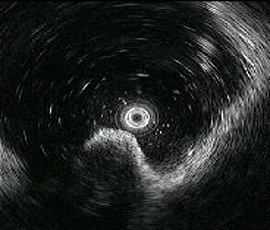

[胃GIST(消化管間質腫瘍)] 手術:腹腔鏡下胃局所切除術(ESD併施)

超音波内視鏡画像